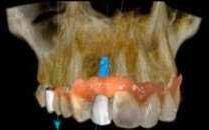

A maradó fogak gyökérreszorpciója patológiás folyamat. Az elváltozások elhelyezkedése alapján csoportosíthatjuk őket külső és belső reszorpciós folyamatokra. A külső gyökérreszorpciók egyre gyakrabban diagnosztizált formája a külső nyaki reszorpció (angolul External Cervical Resorption, ECR) [1. és 2. kép]. Az ECR egy komplex elváltozás, amely egyszerre érintheti a fog keményszöveti állományát, a parodontális szöveteket és előrehaladott esetben a pulpaszövetet is. A modern diagnosztikai eszközöknek köszönhetően egyre gyakrabban és egyre korábban kerül diagnosztizálásra ez a típusú lézió, így a kezelése is egyre inkább a mindennapi klinikum részévé válik az endodonciával foglalkozó kollégák számára. A 3 dimenziós diagnosztikai eszközök terjedésével felmerült az igény egy 3 dimenziós klasszifikációra. Patel és munkatársai 2018-ban kidolgoztak egy új klasszifikációt, amely segít az elváltozások kategorizálásában és a kezelések tervezésében [1]. A téma aktualitását jól mutatja, hogy ezzel egy időben az ESE (European Society of Endodontology) is kidolgozott egy állásfoglalást a külső nyaki reszorpciók diagnosztikájával és terápiás lehetőségeivel kapcsolatban [2].

Ötvenes éveiben járó páciensünk rutinellenőrzésre érkezett rendelőnkbe. A vizsgálat során felfigyeltünk a jobb felső metszőfogán kialakult, íny alatti elváltozásra. A röntgenfelvételen jól látható a kis méretű (Patel 1Ad) reszorpciós elváltozás [3. kép]

Ötvenes éveiben járó hölgyet fogorvosa irányította hozzánk a bal alsó 4-es fogának nagy méretű reszorpciójával [9. kép]. A hölgy ragaszkodott foga megmentéséhez, így a kezelés megtervezéséhez CBCT felvételt készítettünk a fogról [10. kép]. A felvételen a Patel-féle klasszifikáció szerinti Patel 3Ap reszorpciós elváltozás látható. A szájüregi vizsgálat során a fog bukkális felszínén gyulladt ínyt, mély parodontális tasakot és a fog nyaki részén, a foganyagon átsejlő reszorpciós lacunát találtunk [11. kép]. A fog szenzibilitás vizsgálat során nem reagált hideg ingerlésre. A pulpális érintettség miatt elvégeztük a fog trepanálását, majd lebenyt alakítottunk a kavitás láthatóvá tételéhez [12. kép]

1. és 2. kép: Külső nyaki reszorpciós elváltozások CBCT képen.Kónuszos felépítmény kapcsolat